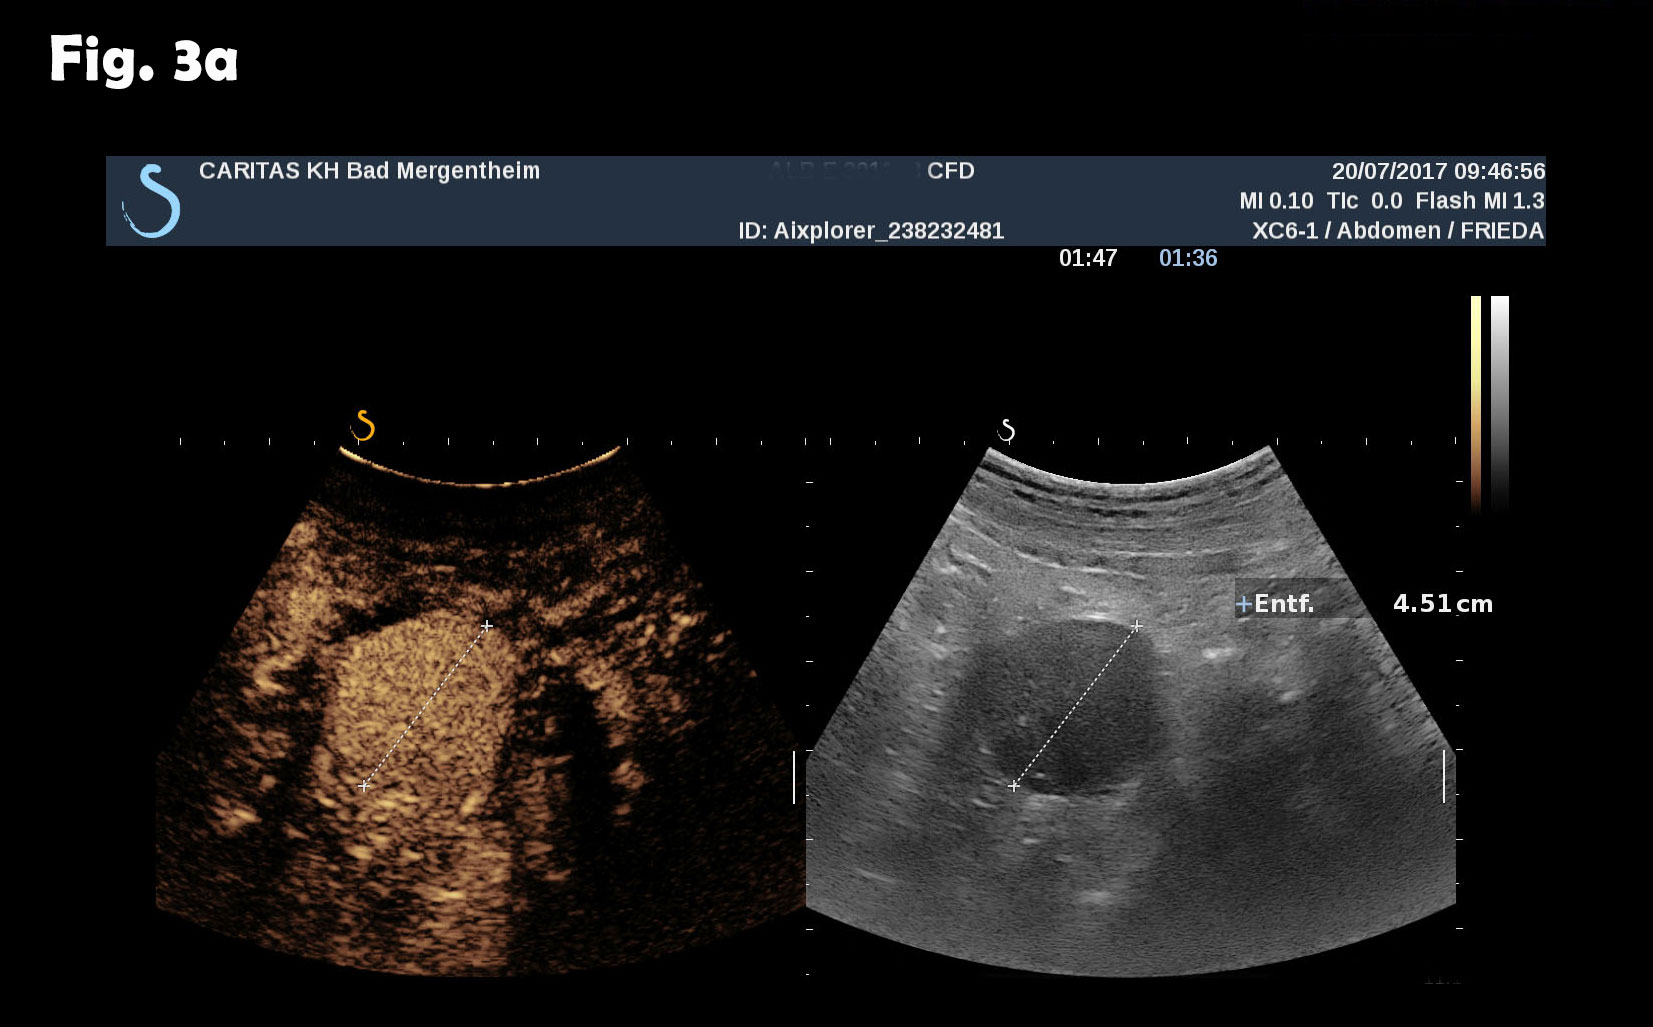

Computed tomography of the chest revealed pneumonic infiltration but was otherwise normal. The endoscopic examination of the upper and lower gastrointestinal tract was normal. Contrast enhanced ultrasound (CEUS) showed arterial and late phase enhancement lasting more than 5 minutes in all examined nodules. After Biopsy the ultrasound examination was performed showing multiple almost echofree but also echogenic round and oval shaped focal peritoneal masses with a size of up to 46 mm [Figure 2-4].

Figure 3: The same lesion as shown in Figure 2. Contrast enhanced ultrasound revealed arterial (a) and late phase enhancement lasting > 4 minutes (b).

Figure 4: At different abdominal locations more echogenic round oval lesions upt to 30 mm were identified by ultrasound. The lesions were best depicted during the late phase enhancement behind the accessory spleen next to the lesion shown in figure 2 (a) and elsewhere in the abdomen (b). The Figure 3c represents the CT finding shown in figure 1.